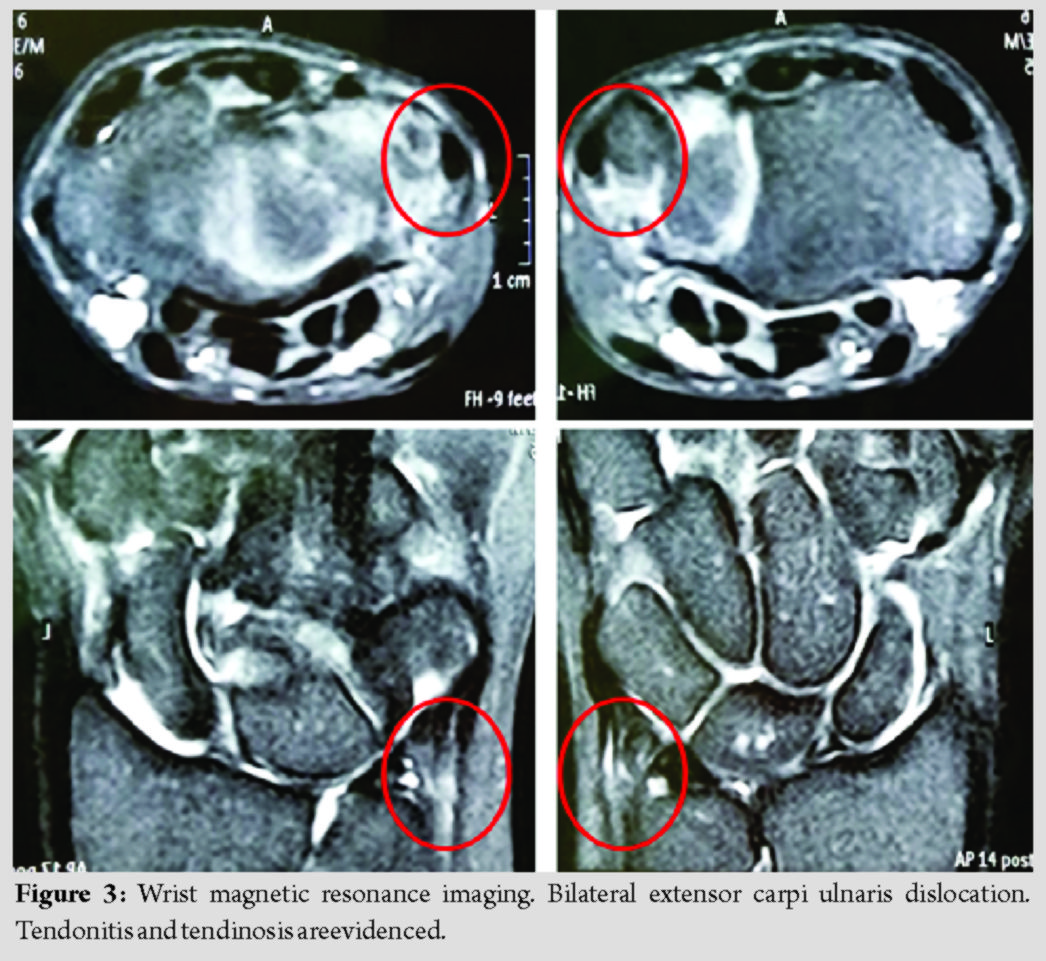

The patient’s initial assessment included visual analog scale (VAS), Quick-Disability of the Arm, Shoulder, and Hand (Q-DASH), and the modified American Shoulder and Elbow Surgeons (m-ASES)scores. VAS for wrists and elbows happened to be 7 and 5, respectively. Pre-operative Q-DASH and m-ASES scores were 33 and 45, respectively. Plain radiographs were performed with no pathological findings. A magnetic resonance imaging disclosed bilateral ECU dislocation together with tendonitis and tendinosis (Fig. 3).